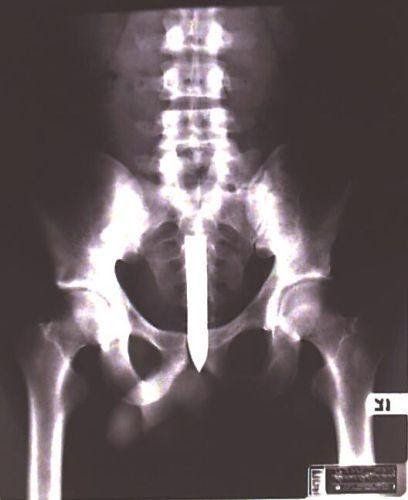

Edged Weapons

Below is a slideshow from the Police Magazine that shows different types of Edged Weapons made by gang members. Some are easily recognizable – others are not. Scroll within the window as needed and use the arrows to navigate through the slideshow.